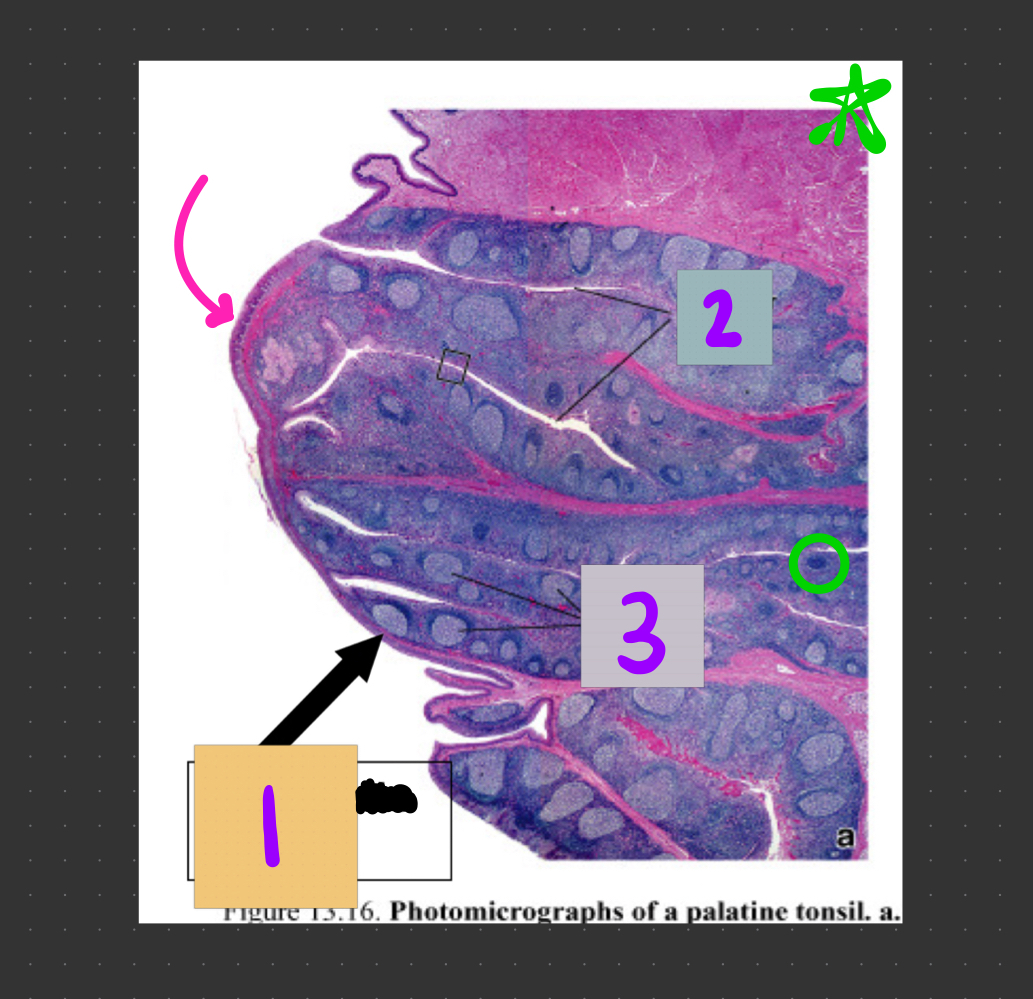

What is #1?

1° lymphoid nodule

dark color, no germinal center

What is #2?

What is #3?

A

What type of epithelium is the pink arrow pointing to?

stratified squamous epithelium

What structure is #1?

lymphatic nodule

What structures are #2?

tonsilar crypts

What structures are #3?

lymphatic nodules

What structure is circled in green?

1° lymphoid nodule (inactive) = no germinal center